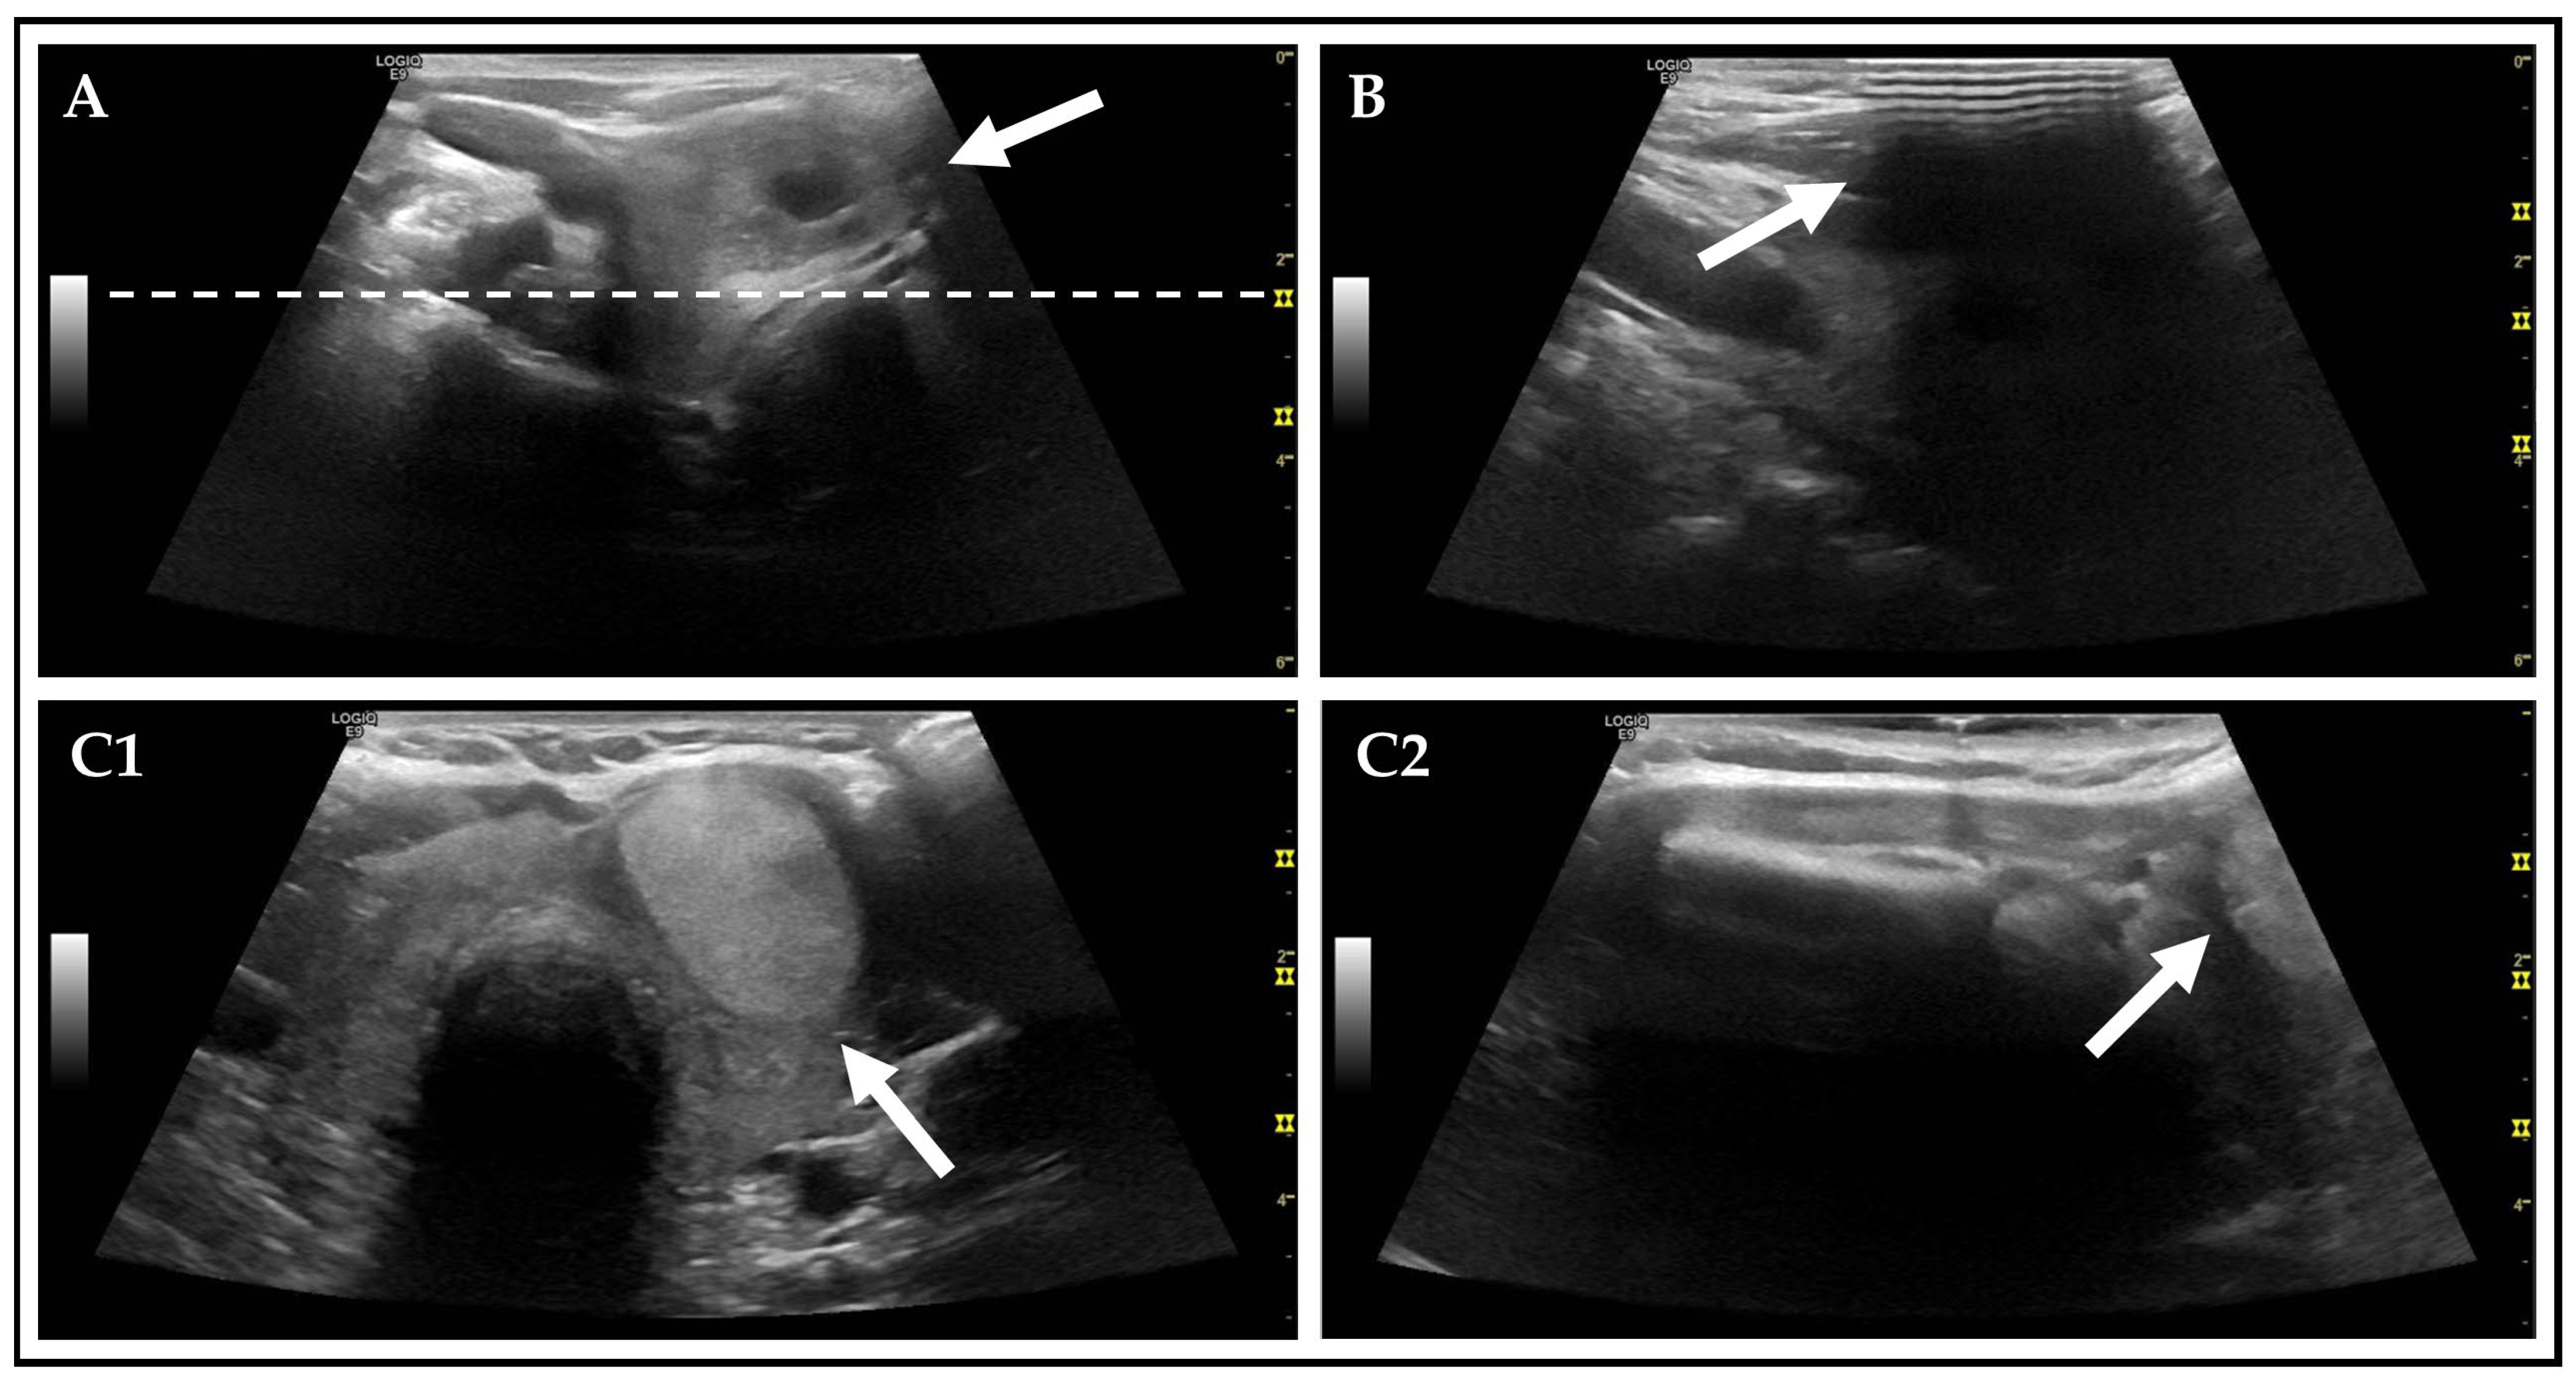

| None | 263 (62.0) | 360 (84.9) | p < 0.001 |

| Poor image quality | 116 (27.4) | 24 (5.7) | p < 0.001 |

| Acoustic shadowing due to… | 64 (15.1) | 41 (9.7) | p = 0.016 |

| None | 247 (58.3) | 357 (84.2) | p < 0.001 |

| Poor image quality | 123 (29.0) | 21 (5.0) | p < 0.001 |

| Acoustic shadowing due to… | 77 (18.2) | 49 (11.6) | p = 0.007 |

| AFTNs incompletely displayed | 73 (17.2) | 5 (1.2) | p < 0.001 |

| Lower pole | 39 (9.2) | 3 (0.7) | p < 0.001 |

| Central | 19 (4.5) | 1 (0.2) | p < 0.001 |